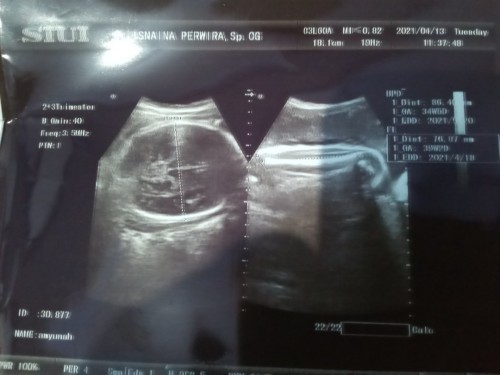

Telat dr hpl 6hari.alhamdullh Lahir dgn normal

Alhamdullh puji syukur kpdmu ya rob. Telah lahir putriku yg ke 2 pd hari kamis jm 5:10 ..priksa ke bidan jm 1:30 uda pembukaan (3).dan skitar jm 4 sore aq kmbali priksa ke bidan baru pembukaan (4).alhamdullh tdk lama kmudian si dede launching dgn normal sehat selamat.d jam 5:10menit.pdhl 2hari sebelum'y.sy sdh merasa down.campur aduk d pikirn krn d sarankn oleh dokter utk sc scpt'y pling lmbat hari sabtu.tp allah berkehendak lain..alhmdullh ya allah tak hnti'y ku ucpkn syukur kpdmu ya rob.😍😍😍 #alhamdulilah